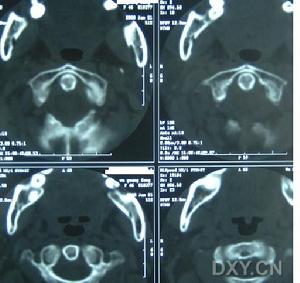

先天性肌斜頸2.頸椎椎骨畸形多系先天性椎骨融合畸形所致火罐網可根據X線平片所見及對胸鎖乳突肌檢查等加以鑑別。

本症多系先天性枕頸部畸形所致,包括短頸畸形、顱底凹陷、半椎體畸形、寰枕融合及齒狀突發育畸形。上述疾病可造成斜頸及面部不對稱,但一般不會產生胸鎖乳突肌的典型條索狀攣縮帶及腫塊,X線檢查可明確上述診斷。